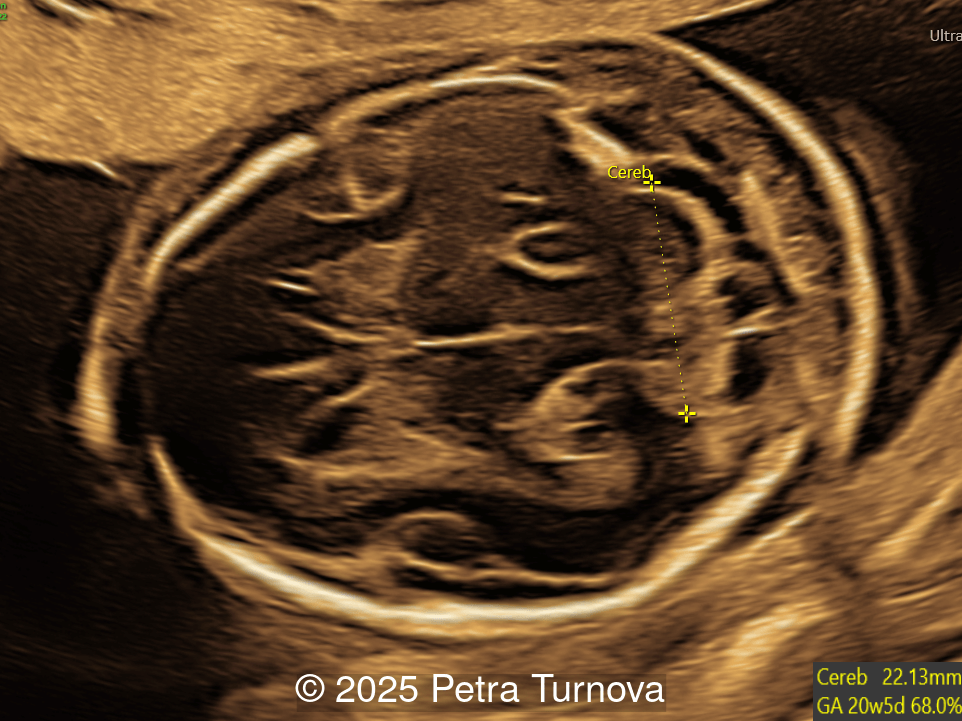

We present a case of Arthrogryposis multiplex congenita with Pena-Shokeir phenotype. Microarray analysis revealed a 240kb duplication of chromosomal region 6q23.3 which includes the genes AHII1 and LINC00271. The Abelson Helper Integration Site 1 (AHI1) gene is associated with Joubert syndrome which is characterized by hypotonia, nystagmus, abnormal respiratory activity, and central nervous system anomalies such as hypoplasia of the cerebellar vermis, polymicrogyria, and corpus callosum malformations. Molecular genetic testing using the Multiplex Ligation-Dependent Probe Amplification (MLPA) method did not demonstrate any mutations in SMN genes, which are related to spinal muscular atrophy. The patient opted for termination of pregnancy.

This is the first case report of Joubert syndrome associated with arthrogryposis multiplex congenita. Joubert syndrome is characterized by hypotonia, abnormal ocular movement, hyperpnea, developmental delay, hypoplasia of the cerebellar vermis and brainstem malformation. The molar tooth sign seen on axial MRI of the brain is a characteristic finding in Joubert syndrome and demonstrated by triad of malformations including (1) a deepened interpeduncular fossa with narrow isthmus, (2) thickened, elongated and horizontally oriented superior cerebellar peduncles as a result of the absence of normal decussation and (3) a variable degree of vermian hypoplasia. Mutations in nine genes have been implicated in Joubert syndrome, including AHI1 [18].